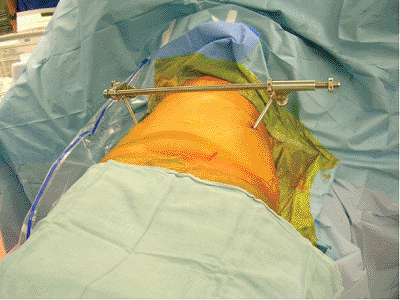

the pelvic ring rapidly. When possible, the pelvic external-fixation

system is applied through use of iliac crest pins inserted after a

closed reduction is obtained and maintained by the circumferential

pelvic wrap. Access holes are cut in the sheet overlying the iliac

crest. The skin is prepped and the pins inserted between the iliac

cortical tables. We recommend application of such devices using the

fluoroscopy unit in the angiographic suite when possible. The

circumferential wrap can also be adjusted through use of the same

imaging unit to assess and adjust the pelvic closed-manipulation

reduction. If the reduction has been achieved, iliosacral screws can

also be inserted using access portals in the sheet (Fig. 39.3).

Figure 39.3.

This morbidly obese adult female pedestrian was struck by a vehicle. She suffered a right-sided, pertrochanteric, closed-femur fracture and bilateral, unstable, pelvic-ring disruptions. A circumferential pelvic sheet provided an excellent closed reduction of the pelvic injuries. With the circumferential sheet in place, the physician made a surgical portal by cutting a portion of the sheet away without compromising its function. The area was prepped and draped, and iliosacral screws were inserted to stabilize definitively the left hemipelvis. The right-sided posterior-pelvic injury was stabilized next through the same technique. The sheet was removed and the reductions were maintained. Her abdominal obesity prevented anterior-pelvic external fixation. |